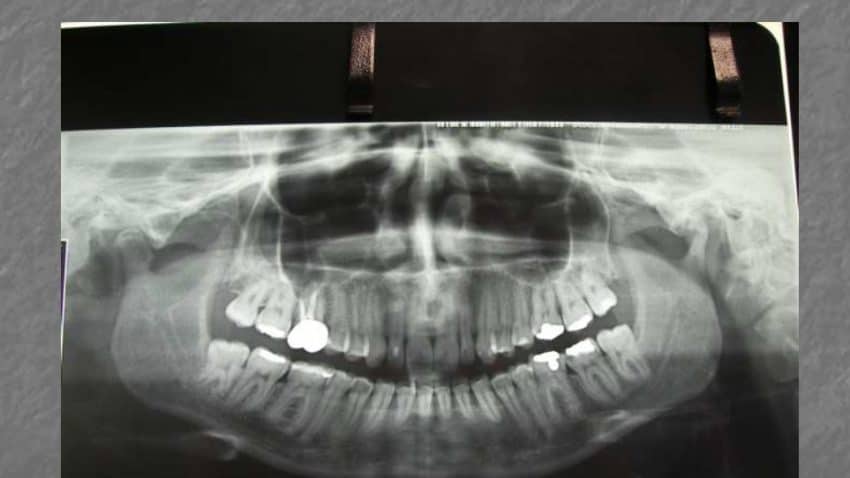

ORTOPANTOMOGRAFIA

– Asimmetrie del corpo o delle branche montanti mandibolari.

– Grossolani quadri degenerativi.

– Stato dentale.

– Lesioni interessanti il n.alveolare inferiore